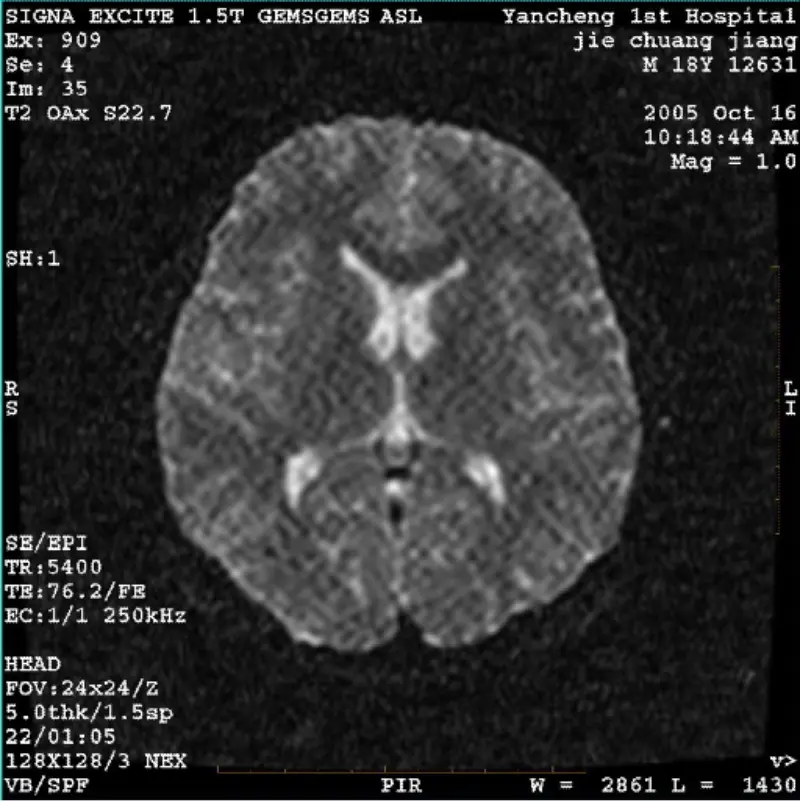

Přečtěte si víceSYSTÉM: 1.5T Signa Twin Excite II (verze softwaru 11.0M4) PROBLÉM/SYMPTO DWI (režim přiblížení a celý režim) a fiesta (režim přiblížení a celý režim) mají obraz viditelný síťový nebo manšestrový artefakt bez ohledu na to, zda používáte tělesnou cívku nebo hlavu cívka, jiný rutinní obraz se zd......